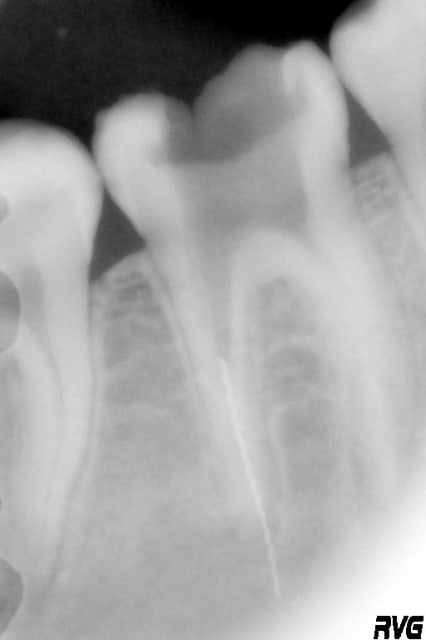

Suite à une nouvelle consultation d'une patiente de 16 ans, dévitalisation de 46 (entre autres) a été décidée (voir plus bas la radio pré-op).

1ere : pré-op